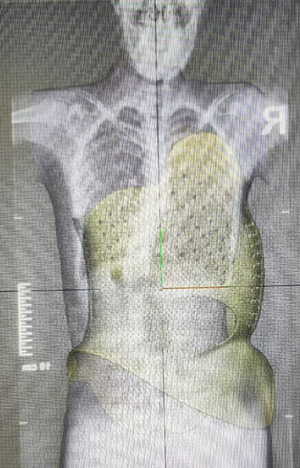

穿著支具到醫(yī)院拍x光片